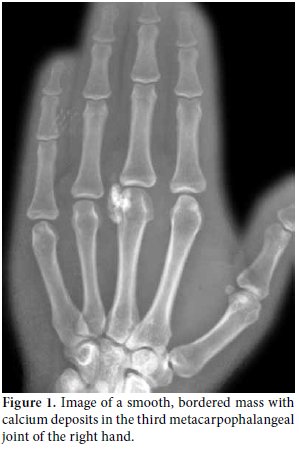

A 30-year-old female patient came to our clinic complaining of pain and swelling in the third metacarpophalangeal joint of the right hand. She described a slowly growing mass and progressively increasing pain in this joint, especially when she made a fist. A semi-rigid, fixed mass of approximately 2.5x1 cm in size was palpated in the physical examination of the patient, but there was no redness or feeling of heat emanating from it. Hand functions, such as grasping or holding, along with finger mobility were within normal limits. In addition, the patient had no other systemic symptoms or findings of arthritis such as fever, arthralgia, or swelling in the joint. A mass composed of calcium deposits was present in the third metacarpophalangeal joint of the right hand in the X-ray radiographs (Figure 1). The patient's medical history revealed nothing of consequence, and the plasma uric acid level and other routine preoperative blood tests were within normal limits, except for a slightly elevated level of the plasma pseudocholinesterase enzyme activity. While the mass lesion was dissected from the surrounding soft tissues, a milky fluid was discharged, A 2.5x1x0.5 cm size rubbery mass with a rigid center was then removed (Figure 2). Amorphous monosodium urate crystal bands surrounded by macrophages, lymphocytes, and multinuclear giant cells together with fibroblastic proliferation associated with tophaceous gout were encountered under polarized light in the histopathological examination of the removed mass (Figure 3). A detailed physical examination along with more laboratory tests and radiographs were performed after the histopathological diagnosis, and all were normal. After a one-year follow-up, the patient's plasma uric acid levels were still within the normal limits, and there had been no acute attack of arthritis. The patient was free of pain, and her hand functions were satisfactory.

There may be no findings other than soft tissue swelling surrounding the affected joint in a direct radiographic examination of acute gout arthritis.[17] Radiographic bone changes may be encountered six to eight years after the initial attack in 45% of the patients, but they are not highly specific and sensitive enough for diagnosis.[24] Magnetic resonance imaging (MRI) of tophi in soft tissues is usually nonspecific, and it may imitate neoplasia and infection. Furthermore, variable signal intensities in the T1- and T2-weighted images depend on the difference in the calcium concentration in the tophi.[10,25] Chen et al.[26] reported that calcified tophi are rare in the wrist and that the presence of such calcification probably depends on calcium crystals in conjunction with calcification in the cholesterol stored in the tophi along with an underlying calcium metabolic disorder or bone debris from large joint destruction.[27,28] In our case, there was no evidence except for smooth, bordered calcium deposits in the radiological evaluation.